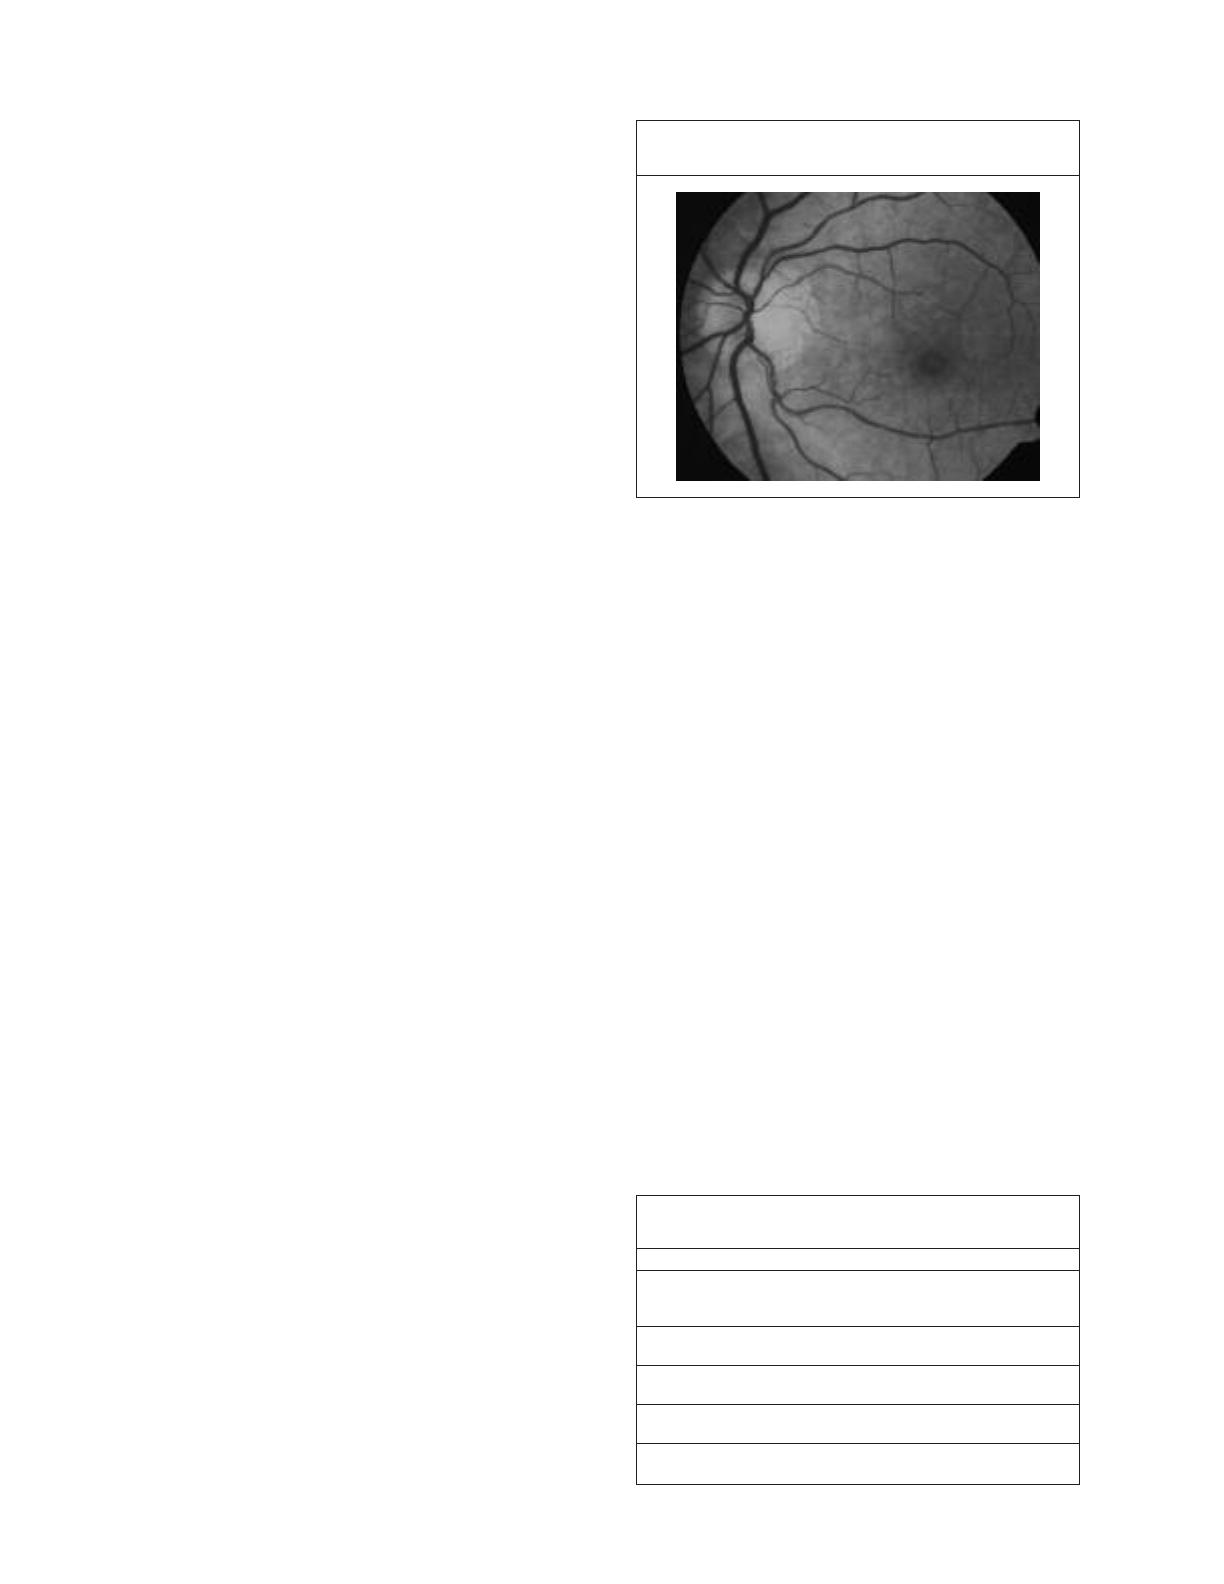

La TCO fera la différence entre un trou lamellaire et

un trou maculaire. (Figure 3)

Figure 3 : Trou lamellaire. Il y a encore du tissu

au dessus de l’EPR

EPR